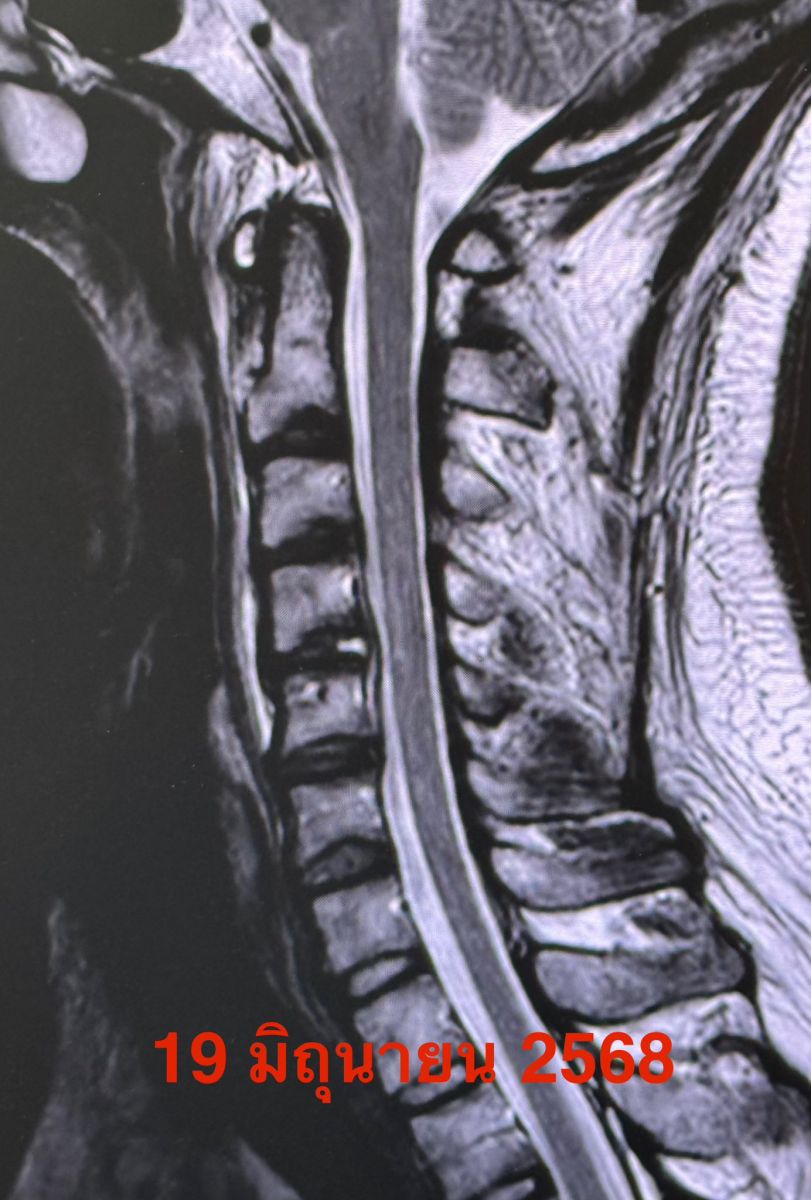

วันที่ 7 มิถุนายน 2568 มีไข้สูงหลังกินอาหารนอกบ้าน หลังจากนั้น 2 วันไข้ลงเอง เริ่มปวดต้นคอและไหล่ข้างขวา ขยับคอลำบาก ทำกายภาพไม่ดีขึ้น ตรวจคลื่นแม่เหล็กไฟฟ้าของกระดูกต้นคอ MRI

วันที่ 19 มิถุนายน สงสัยหมอนรองกระดูกต้นคอระหว่างข้อที่ 4 และ 5 อักเสบ (Discitis) อาการปวดไม่ดีขึ้น ทำ MRI ซ้ำ